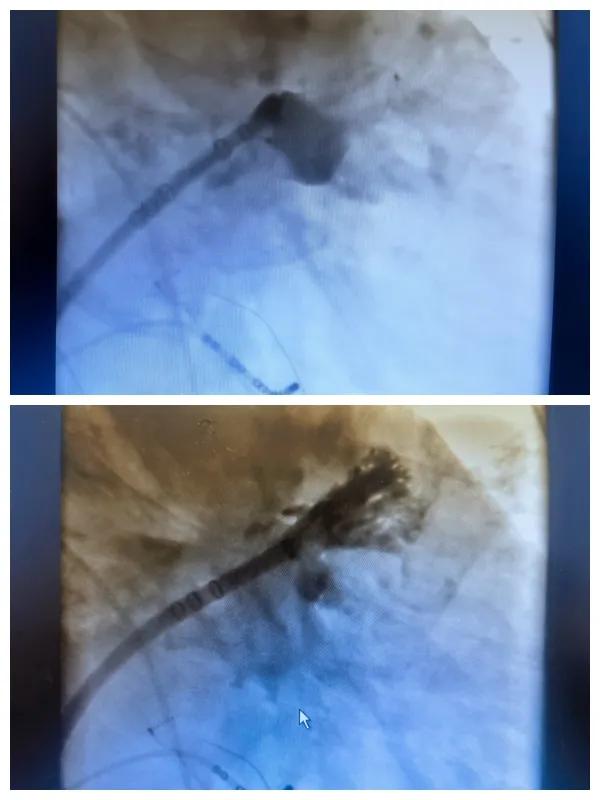

6月26日,市二院成功為一名老年房顫患者實(shí)施了房顫射頻消融術(shù)+左心耳封堵WM FLX一站式介入治療,標(biāo)志著醫(yī)院在心律失常介入治療領(lǐng)域邁出了嶄新的一步,開(kāi)啟了新的治療篇章。

為了讓患者得到全面、綜合的治療,經(jīng)過(guò)團(tuán)隊(duì)術(shù)前充分討論,并征得家屬同意,心血管內(nèi)科團(tuán)隊(duì)決定采用目前國(guó)內(nèi)外先進(jìn)的房顫射頻消融術(shù)+左心耳封堵WM FLX一站式介入微創(chuàng)手術(shù)來(lái)治療老人的疾病。整個(gè)手術(shù)過(guò)程圓滿順利,術(shù)后何大爺各項(xiàng)體征正常,蘇醒后順利返回病房。